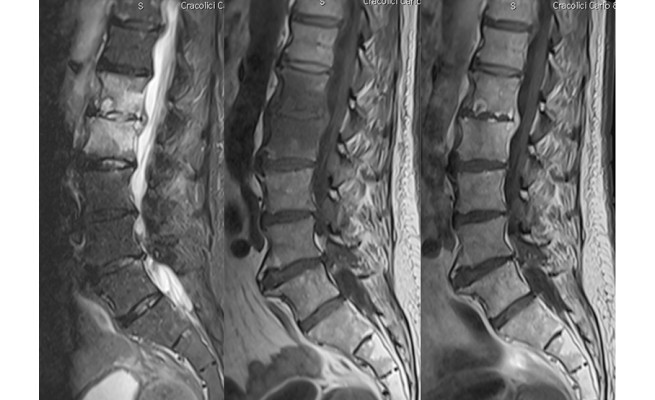

La spondylodiscite infectieuse fait partie des nombreuses causes de rachialgies et est une affection peu fréquente représentant 2 à 7 % des ostéomyélites (fig. 1). Le principal problème de cette infection réside dans la difficulté à la diagnostiquer.